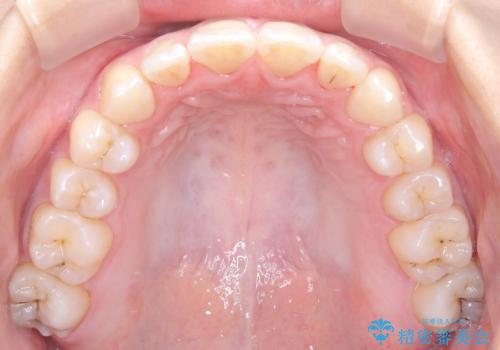

右下第二小臼歯の舌側転移の改善

- 患者様は、右下第二小臼歯が舌側に転移していることが主訴でした。診断の結果、抜歯を伴う矯正治療も検討しましたが、奥歯の遠心移動とIPR(インタープロキシマルリダクション)を行うことで、非抜歯で矯正を進めることが可能であると判断しました。治療計画では、審美ワイヤーを用いた2年間の治療で、歯列を整えつつ、臼歯関係や正中のバランスを維持しながら進めました。

非抜歯矯正では、歯の動きを慎重に調整することが求められます。本症例では、奥歯を遠心に移動させることで、舌側に転移した右下第二小臼歯の位置を改善しました。また、IPRを行うことで歯間スペースを確保し、無理なく歯列の調整を行いました。非抜歯での治療は、特に臼歯関係や正中を保ちながら治療できるというメリットがあり、最終的にはバランスの取れた歯並びを実現できました。審美ワイヤーを使用したことで、治療中も目立ちにくく、患者様の見た目にも配慮した治療を行いました。